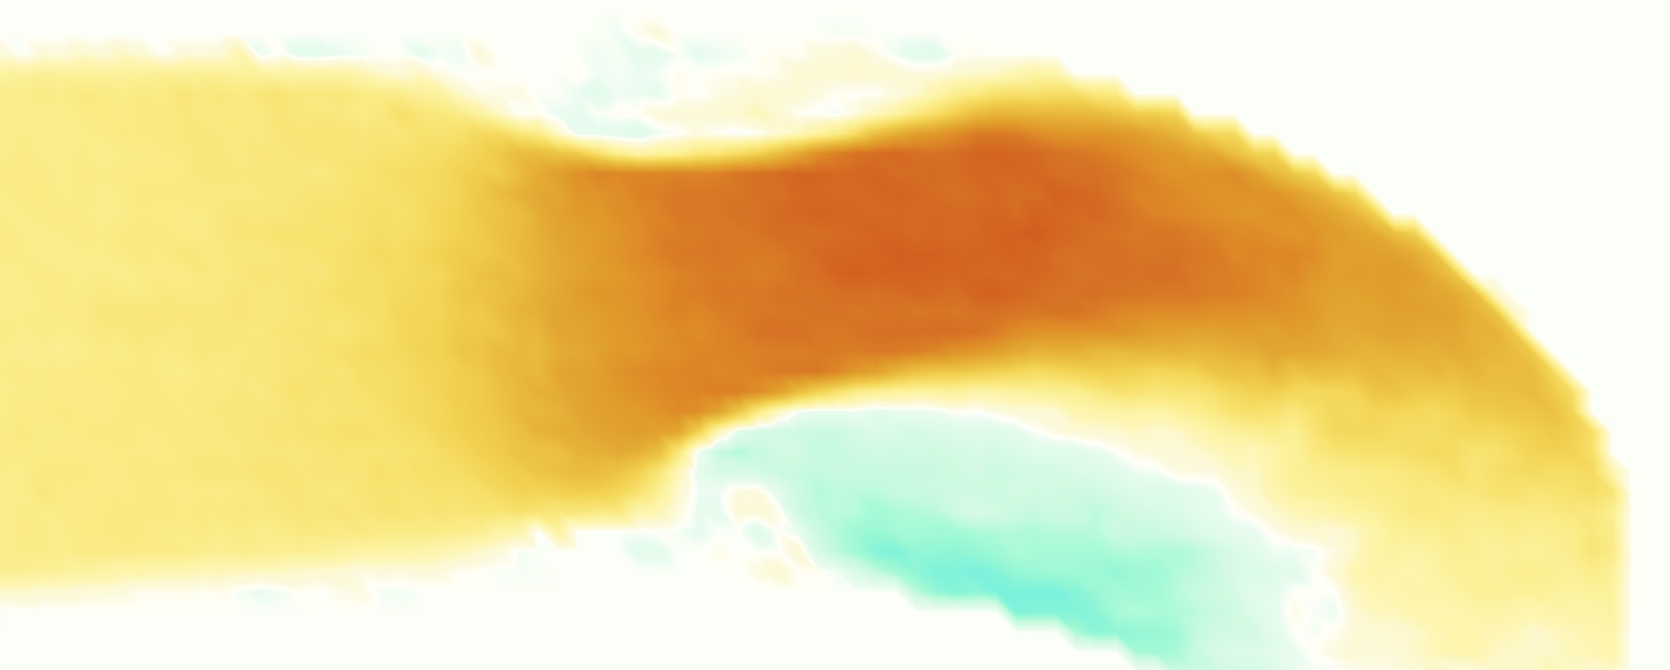

The emergent hemodynamics showed excellent qualitative agreement with experiments. Slice views of the axial component of fluid velocity ( component) in the sagittal plane that cuts through the center of the vessel, parallel to the flow direction, are shown in Figure 5. The flow in both the simulation and the experiment began to accelerate at the same time, with a jet forming through the open valve leaflets. The velocity, angle, and shape of the jet agreed well between the two cases during systole. The simulation captured the slight upward angle of the jet, which was not fully centered in the vessel. It also matched the location where the jet impacts the wall and the slower speed of the jet as it turns with the MPA downstream. As the flow decelerated, the fluid along the interior curve of the vessel reversed first while forward flow persisted where the jet was strongest, as seen in both the simulation and experimental results.

In both the experiment and the simulation, a separation region of reverse flow developed along the interior curve of the vessel under the core jet through the valve. The reverse flow began to develop at the same time in the cardiac cycle and grows throughout systole. The simulation lacked reversed flow in the entire region where reversed flow was present in the experiment, but this region developed some flow separation and had much slower flow than elsewhere in the vessel. Thus, the simulation captured that this is a distinct region from the core jet through the valve opening. There was a smaller amount of slower and slightly reversed flow along the outer curve of the vessel, close to the valve annulus and scaffold support. This region was well-matched between the experiment and the simulation.